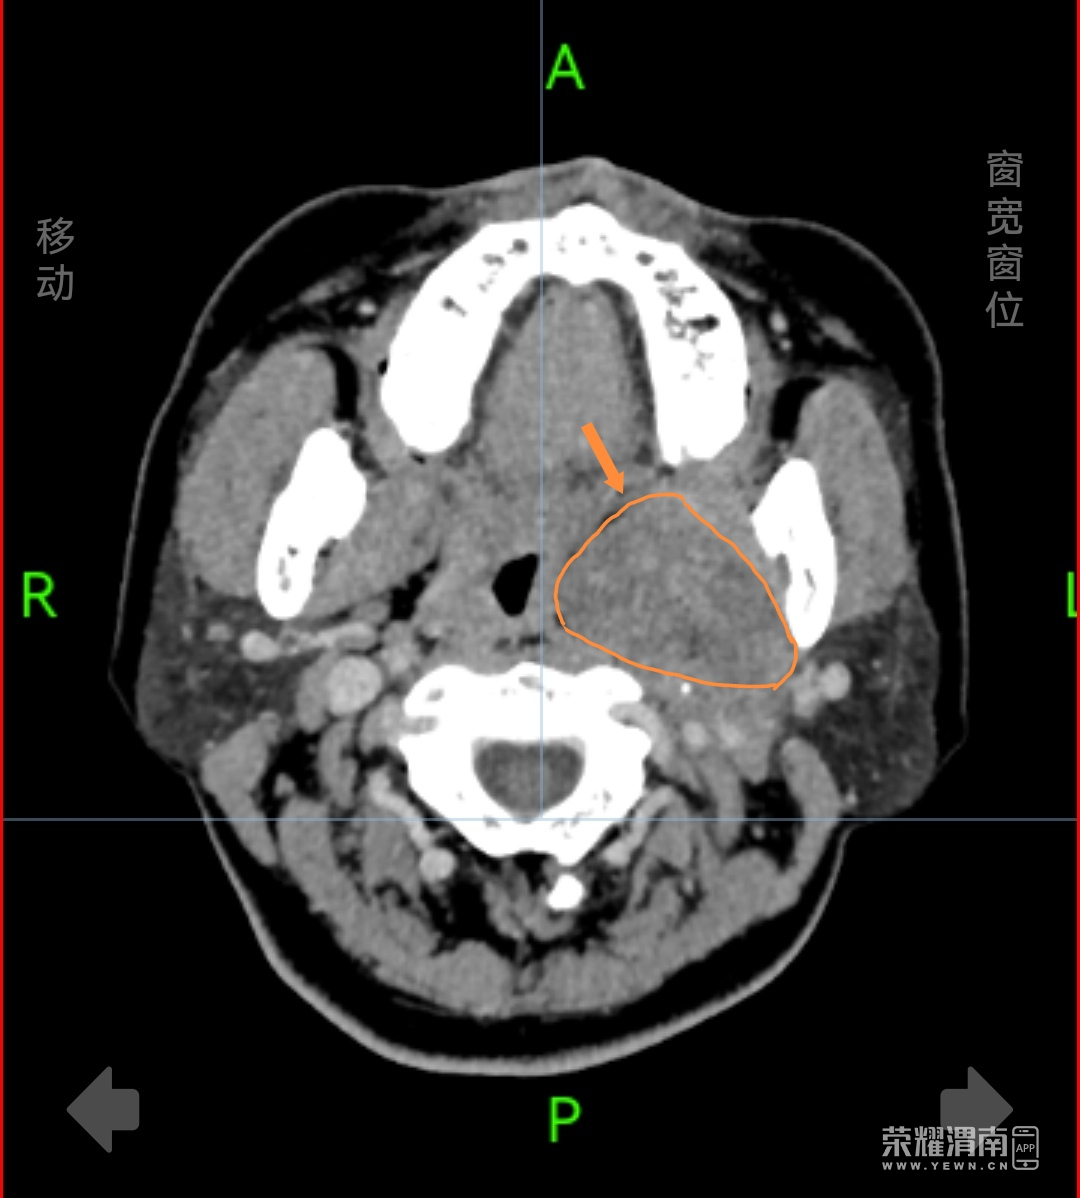

患者杨女士(化名),44岁,在体检颅脑CT检查中发现咽旁间隙存在一处大小约7×6×6厘米的肿物。这个位置特殊——咽旁间隙是位于颈部深处的潜在腔隙,周围毗邻颈内动脉、颈内静脉、颅神经等重要结构,传统手术需要从颈部外部做切口,创伤大、风险高,且术后可能遗留明显疤痕。为寻求更佳治疗方案,杨女士来到渭南市中心医院就诊。

咽旁间隙肿瘤手术一直是耳鼻喉头颈外科的技术难点。科室主任宋建涛介绍,传统手术需在颈部切开约8-10厘米切口,创伤较大,恢复周期长,且存在损伤面部神经等风险。经科室详细讨论,医疗团队决定为患者施行经口内镜下肿物切除术。

手术在麻醉科协作下进行。耳鼻喉头颈外科团队借助内镜系统放大显示手术区域,清晰观察肿瘤与周围血管、神经的解剖关系。凭借丰富解剖经验与内镜操作技术,医生在有限空间内仔细分离肿瘤组织,完整保留重要血管与神经。手术历时两个多小时,肿瘤被完整切除,术中出血约50毫升。

据参与手术的副主任医师赵海军介绍,手术关键在于在狭小空间内完整切除肿瘤的同时,保护好周围重要结构。内镜提供的清晰视野与照明,为精细操作提供了保障。